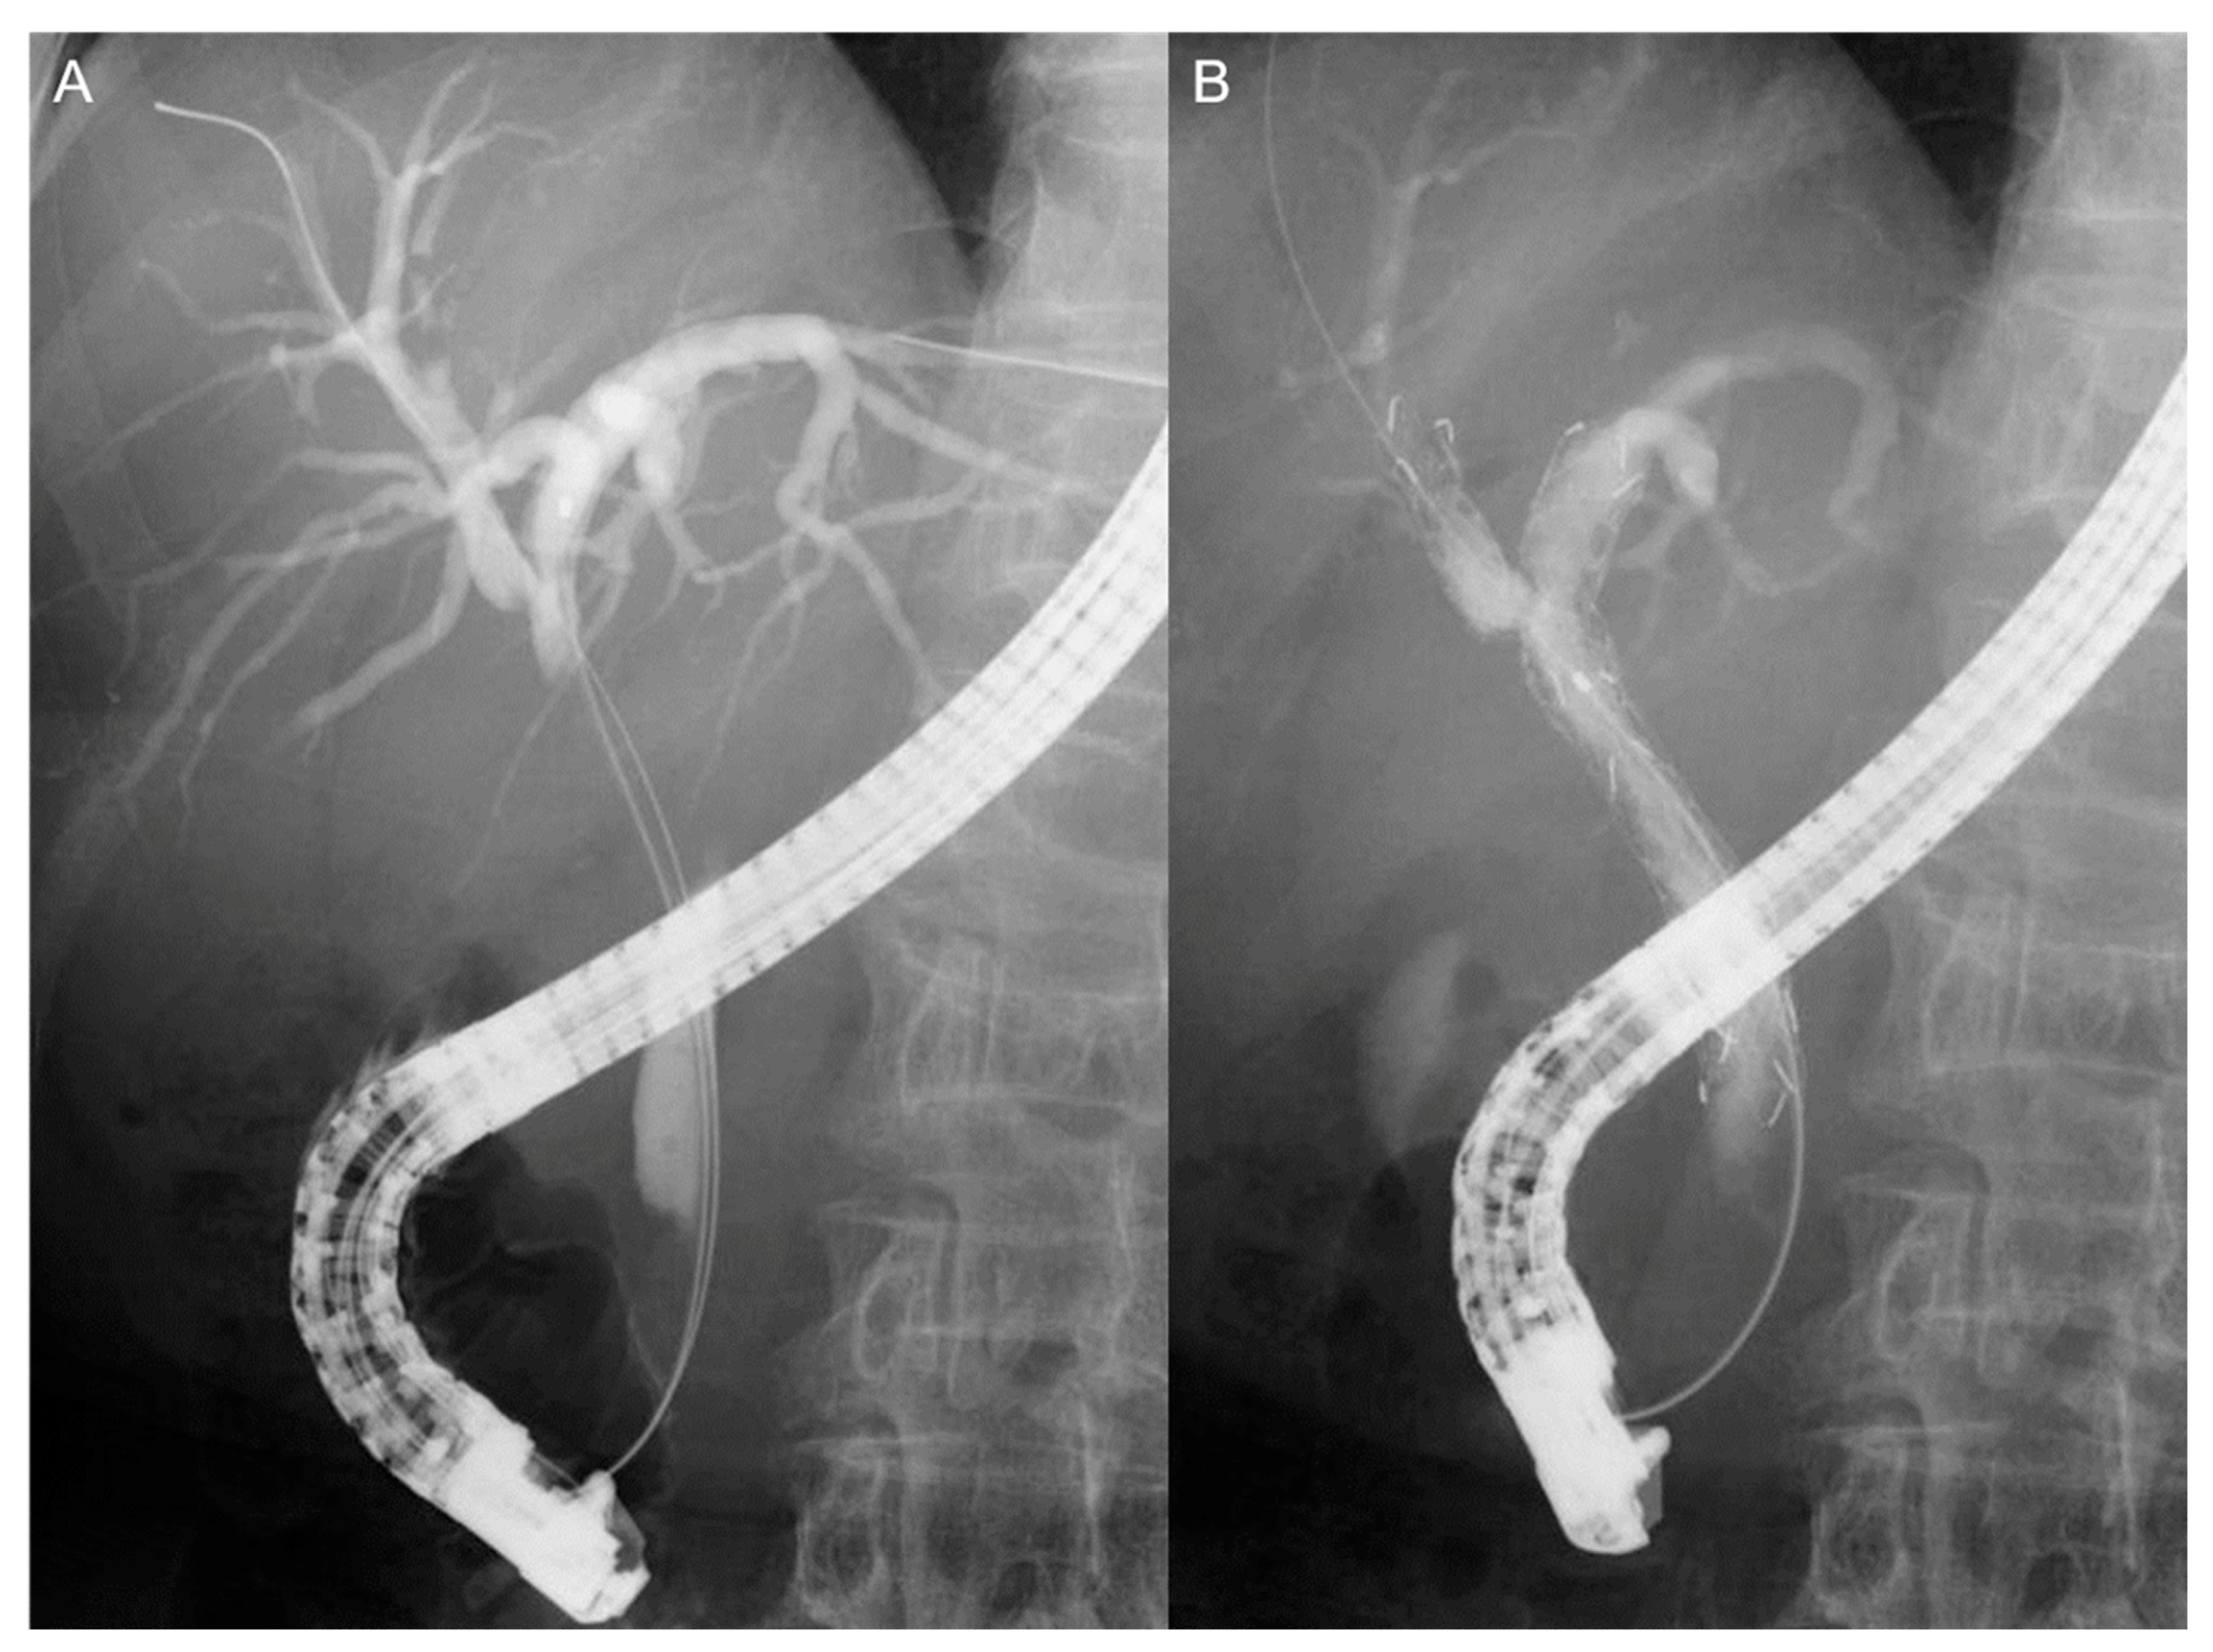

2.6. Endoscopic Procedures